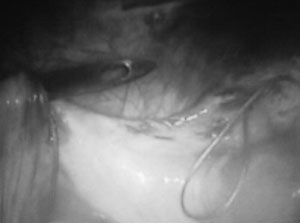

Εικόνα 3. Η βελόνα διαπερνά

τον κυστεοορθικό χώρο και την κολπική μεμβράνη. Πριν και μετά τη διάτρηση ο

χειρουργός ελέγχει το ορθό και την ουροδόχο κύστη (με δακτυλική εξέταση και

κυστεοσκόπηση).

Εικόνα 4. Η κολπική μεμβράνη

διαπερνάται στο κέντρο της και συλλαμβάνονται τα δύο ράμματα που στο άλλο άκρο

τους είναι ενωμένα με την ακρυλική ελαία.